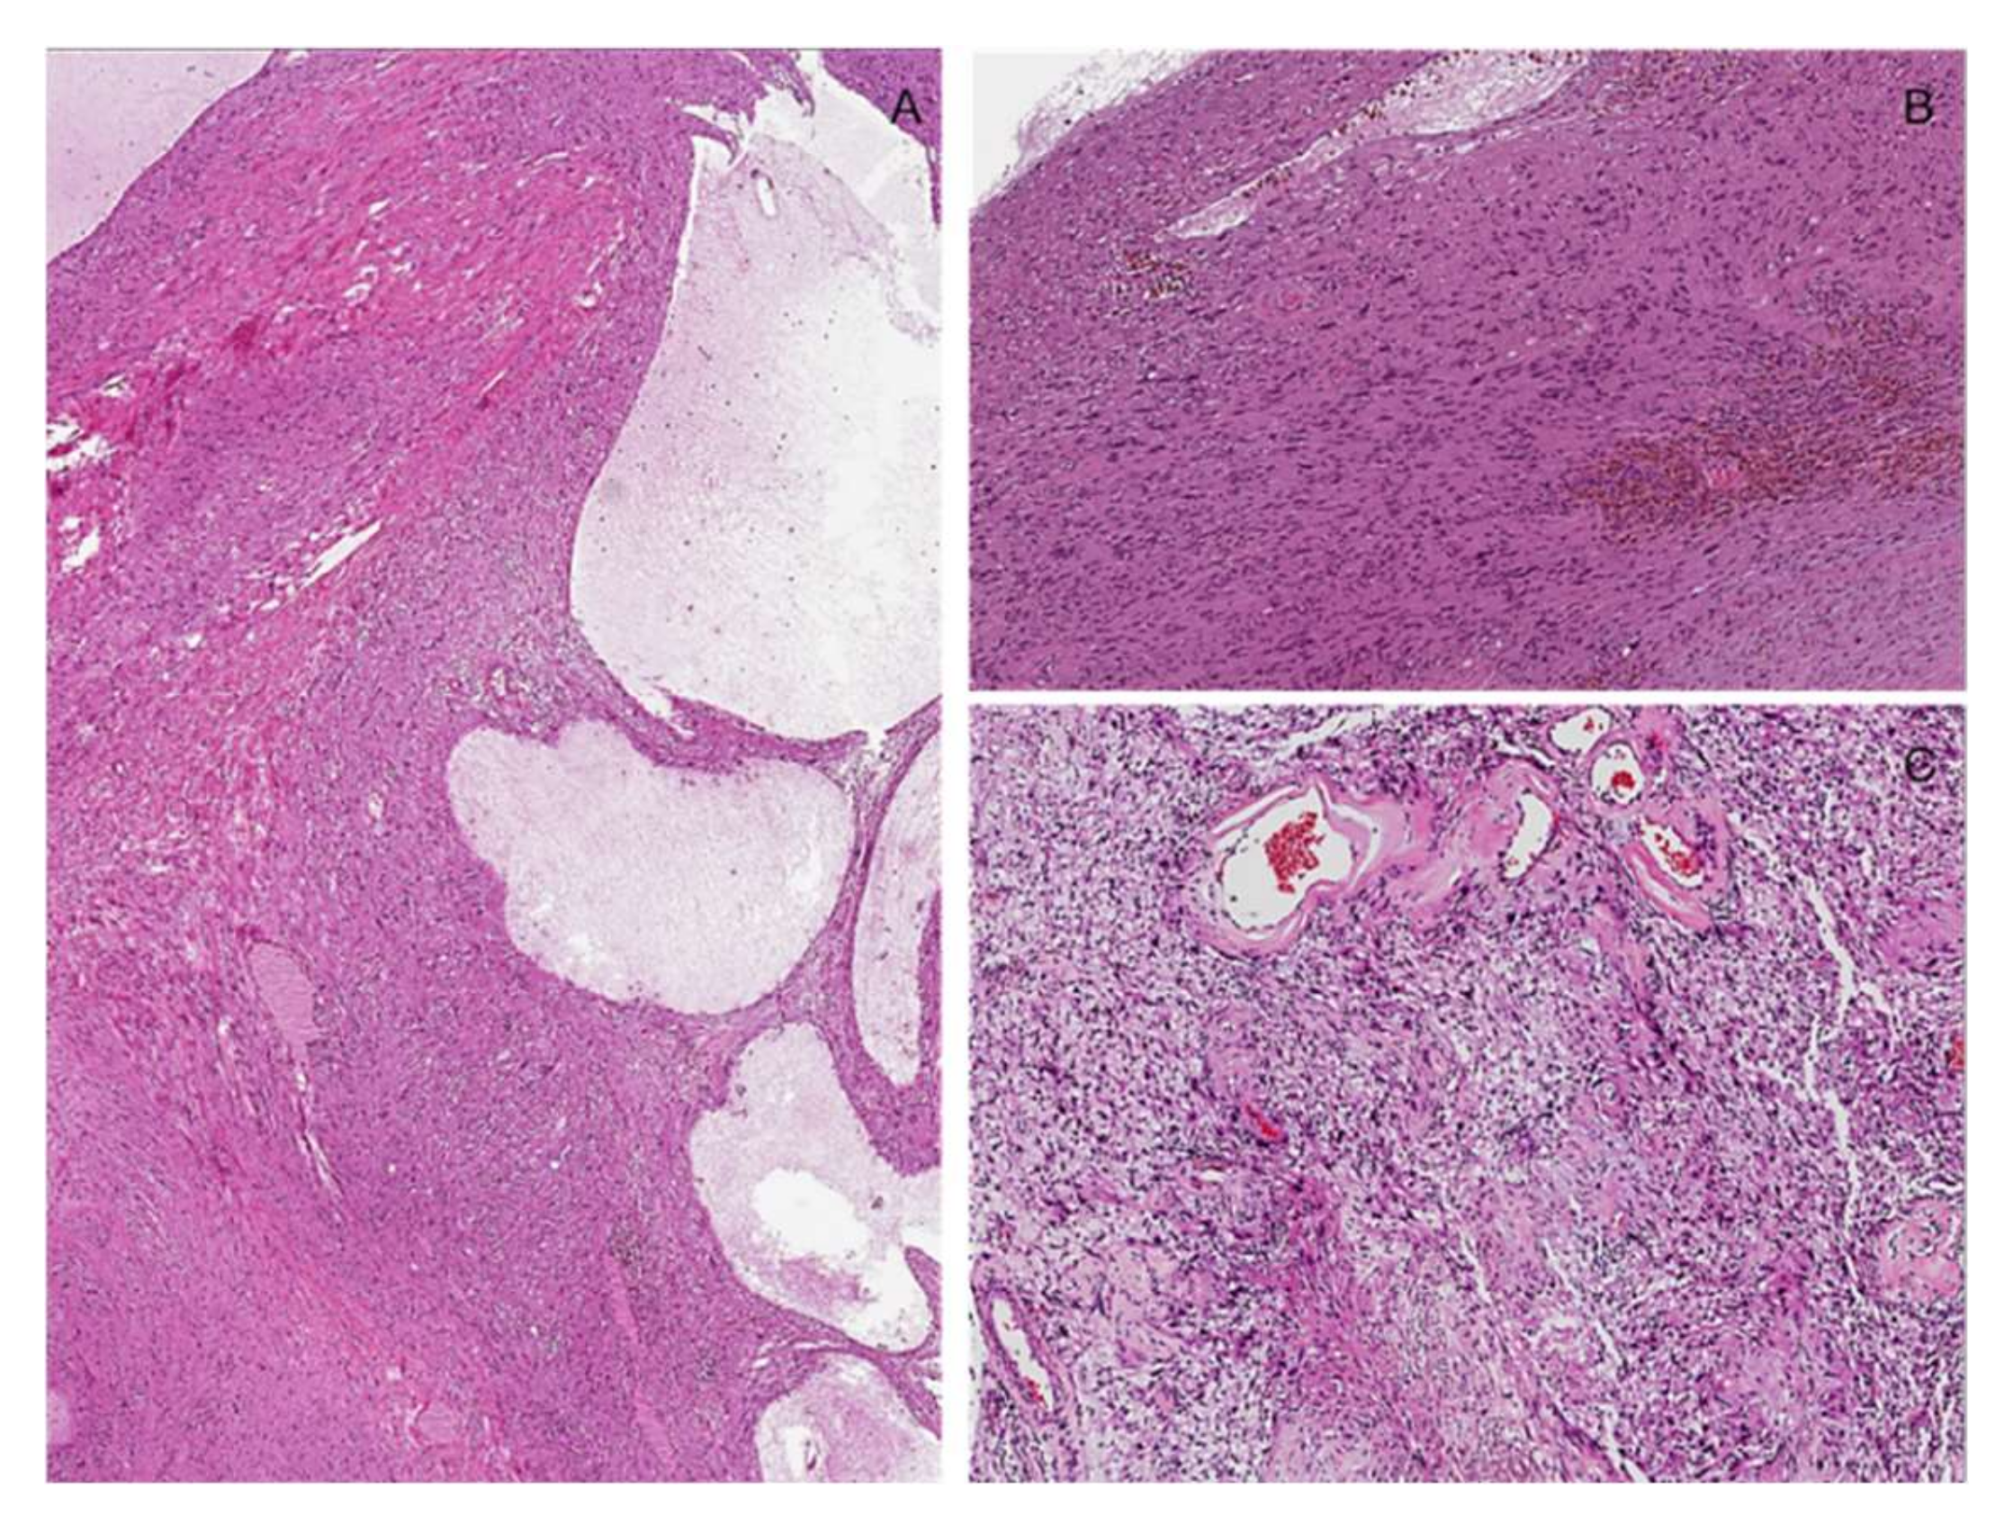

3.3. Plexiform Neurofibroma

3.4. Potential Morphological Pitfalls of Malignancy in Neurofibromas: Cytological Atypia and Hypercellularity